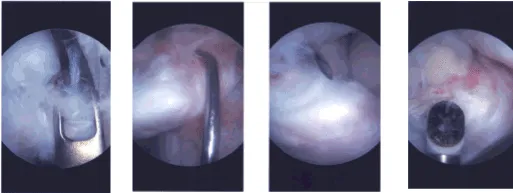

Intraoperative Arthroscopy Images

There was an intact patellofemoral compartment. In the intercondylar notch there could be seen a free fragment from the distal ACL. It was all covered in fibrosis and was held in pieces with the fibrotic tissue. Shaver was used through the debridement.

This was followed by 4.5 mm to decorticate the tibial portion. The femoral portion was decorticated with the use of a shaver so as not to deep off excess bone from there. The ACL was reduced and held in place with an ACL jig and a K-wire was passed to temporarily hold it.

Two intraosseous tunnels were made, one medial and one lateral to be passed and secured. Now, the ACL footprint is used to pass FiberTape x2 through the ACL distal stump. This was passed into the intraosseous tunnel to see the reduction.

The reduction was not appropriate so the lateral lens of the FiberTape was also taken out from the medial intraosseous tunnel and a good reduction could be seen. Once we were able to get a good reduction, lateral parapatellar transverse incision was given to do a mini arthrotomy.

After the reduction, the fracture site could be seen and was inserted into the fracture site and was found to be in acceptable position. This was followed by tightening and knotting of the fiber kits over EndoButton. Arthroscope reduction with a SwiveLock after drilling 5.25 and insertion of 4.75 SwiveLock.